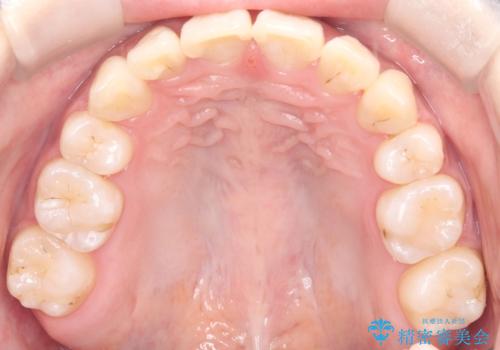

治療の結果、長年気にされていた八重歯と正中のズレが解消し、機能的にも整った理想的な歯並びを獲得。目立たない装置で治療を完遂し、自信を持って笑える美しい笑顔を手に入れていただけました。

正中のズレ: 歯を左右対称に移動させることで、上下の歯の中心線を正確に合わせ、顔全体のバランスも改善しました。

八重歯: 突出していた八重歯を歯列内に誘導し、デコボコを解消しました。